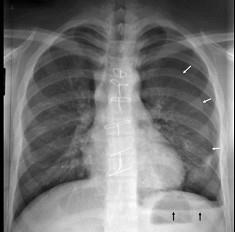

18岁,男,被人殴打后胸痛,请结合胸片选出最可能的诊断 ( )A.血气胸B.气胸C.胸腔积液D.肺气肿E.肺挫伤

问题 18岁,男,被人殴打后胸痛,请结合胸片选出最可能的诊断 ( )

选项 A.血气胸 B.气胸 C.胸腔积液 D.肺气肿 E.肺挫伤

答案 A